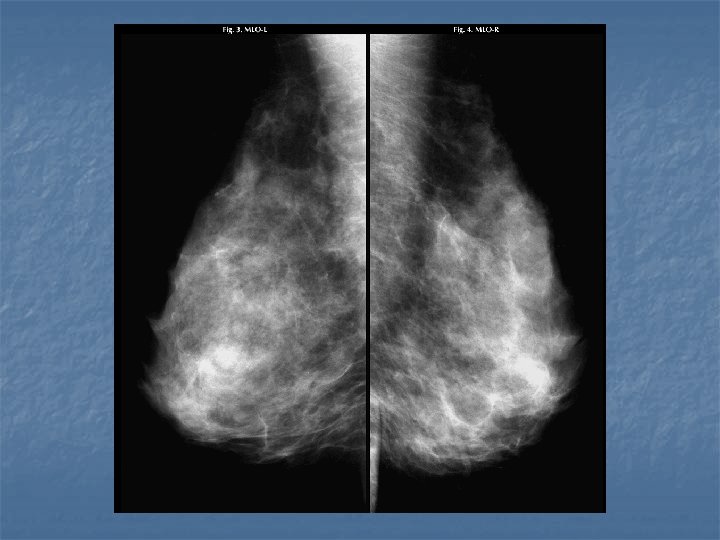

Gynecomastia n n Proliferation of fibroglandular tissues resulting in breast enlargement Hyperplasia of the ductal elements, fibroepithelium, and stroma (lobules do NOT develop) Dense tissues fan out from retroareolar region rather than forming a mass Bimodal age distribution: MC puberty, 5 th decade